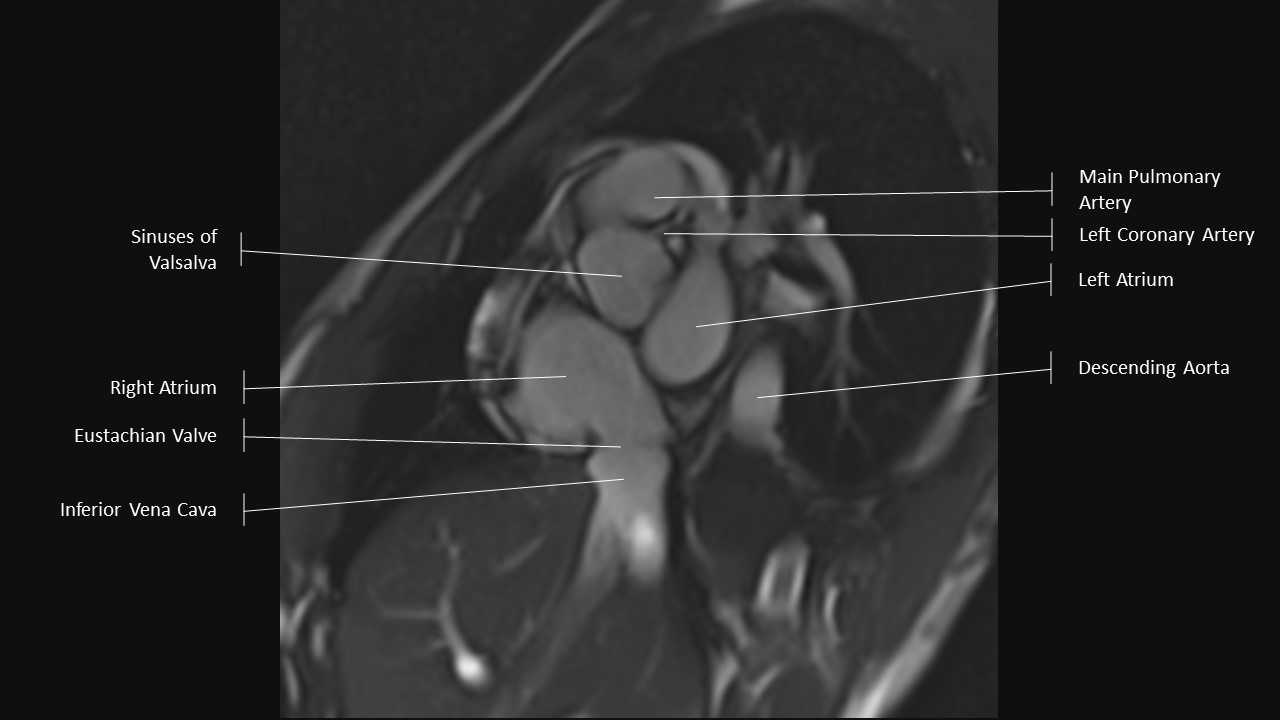

Aortic Root Series